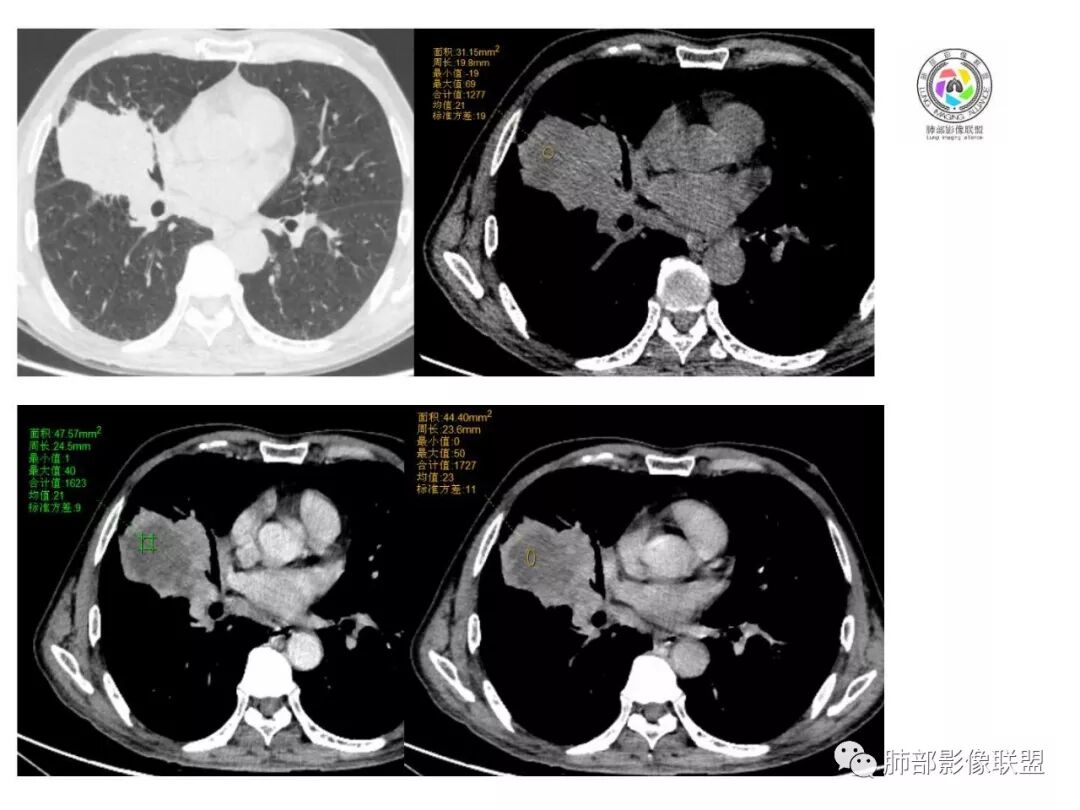

一米阳光:

老年男性,体检发现。

右肺中叶肿块影,向上向下侵犯叶间裂,边缘膨隆,分叶,毛刺。肿块内部密度不均,大片坏死。血管走形尚可。中叶支气管狭窄截断。增强不均匀强化。纵隔淋巴结肿大,部分融合。

考虑恶性,腺癌>鳞癌。鉴别炎肌母。

老年男性,右肺巨大肿块,跨叶生长,见大片状坏死,坏死边界部分清楚,见棘状突起、毛刺及分叶,支气管截断,纵隔内见坏死强化淋巴结,周围肺叶小叶间隔结节样增厚,考虑恶性,腺癌?肉瘤样癌?并淋巴结转移及癌性淋巴管炎

晨读:右中为主肿块,跨叶,右中叶外侧支闭塞,病灶有坏死,远侧少许小叶间隔增厚,考虑恶性,腺癌大于鳞癌。结合有无吸烟史